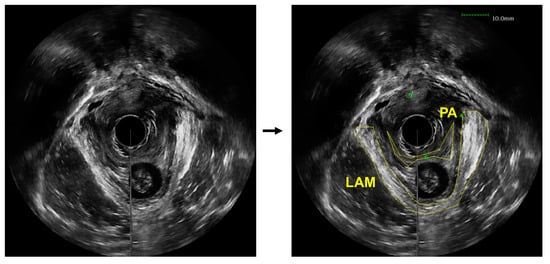

- Asif, Z.; Tomashev, R.; Peterkin, V.; Wei, Q.; Alshiek, J.; Yael, B.; Shobeiri, S.A. Levator ani muscle volume and architecture in normal vs. muscle damage patients using 3D endovaginal ultrasound: A pilot study. Int. Urogynecol. J. 2022. [Google Scholar] [CrossRef] [PubMed]